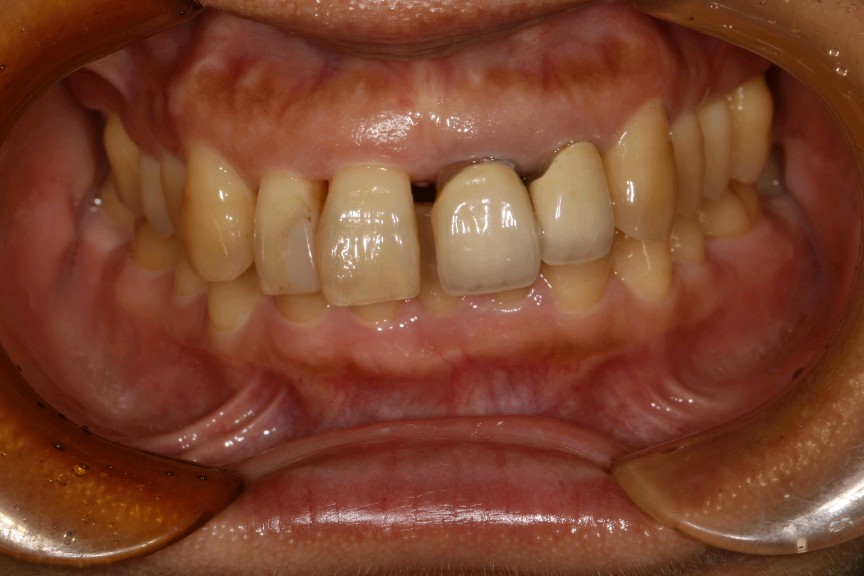

患者女,45岁。患者自述有刷牙出血症状,探易出血,探及牙周袋深度5mm,可探及袋内牙石3mm。21、22已行根管治疗加桩冠修复,牙龈萎缩,边缘不密合,21牙颈部楔缺。中切牙之间缝隙较大。12邻面部分充填物。。X线示根尖无阴影。患者自觉前牙不美观,要求重新修复。

治疗计划:1、牙周治疗。2、21,22饵激光拆除牙冠。清理基牙,重新预备,西诺德全冠修复。3、11、12贴面修复。